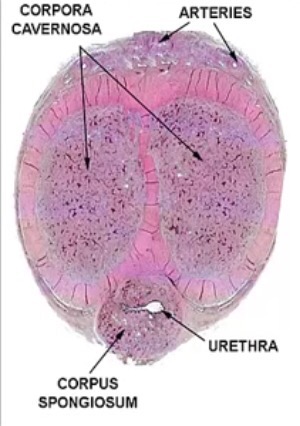

Si miramos una sección de este órgano, veremos que el mismo consiste en un compartimento que alberga a tres cilindros. Al cilindro inferior se le llama «cuerpo esponjoso» y por allí circula la uretra, que es el conducto por donde se expulsan el semen y la orina y que se dobla al final en el glande, cuya función es la de evitar que, durante una erección pueda comprimirse la uretra, y obstaculizarse la salida de los fluidos corporales, pero la parte más significativa de la estructura peneana son los otros dos cilindros parecidos a unas esponjas, llamados «cuerpos cavernosos«.

Estos cuerpos cavernosos son- propiamente- el mecanismo erector del pene y su funcionamiento se basa en los principios de la hidrodinámica. Están formados por unos pequeños globos llamados «espacios lacunares» que tienen la misión de rellenarse de sangre . Con esto se consigue que aumenten hasta cinco veces su tamaño y en eso consiste «la erección«, un proceso regido por las leyes de la hidrodinámica.